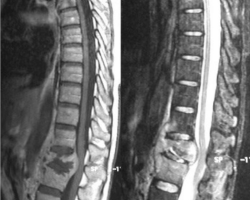

Abcès pré-vertébral